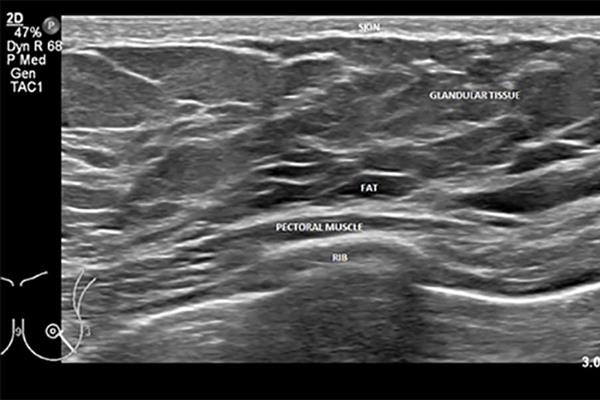

تشخیص مشکلات و بیماریهای پستان و تیروئید با سونوگرافی تخصصی و دقیق.

غربالگری و تشخیص زودهنگام بیماریهای پستان از اهمیت بسیاری برخوردار است و سونوگرافی سینه یکی از ابزارهای اصلی برای ارزیابی دقیق بافت پستان به شمار میآید. در این مقاله، به اهمیت سونوگرافی سینه در تشخیص، غربالگری و فواید آن در شناسایی بیماریهای پستان میپردازیم.

سونوگرافی سینه یک روش ایمن، بدون درد و مؤثر است که با امواج صوتی، تصاویر دقیقی از بافت داخلی پستان به دست میدهد. این روش بهویژه در خانمهایی که بافت سینههای متراکم دارند، نقش مهمی در تشخیص زودهنگام تودهها و ناهنجاریها ایفا میکند. این ویژگی مهم سونوگرافی، آن را به ابزاری ارزشمند در غربالگری و تشخیص سرطان پستان تبدیل کرده است.

غربالگری سینه با سونوگرافی نیاز به آمادگی خاصی ندارد و به راحتی در مراکز رادیولوژی و سونوگرافی قابل انجام است. در این روش، یک ژل مخصوص روی سینه قرار داده میشود و سپس با استفاده از دستگاه سونوگرافی، تصاویر دقیقی از بافت پستان تهیه میشود. این تصاویر به پزشک کمک میکند تا تغییرات موجود در بافت پستان را به دقت ارزیابی کند.